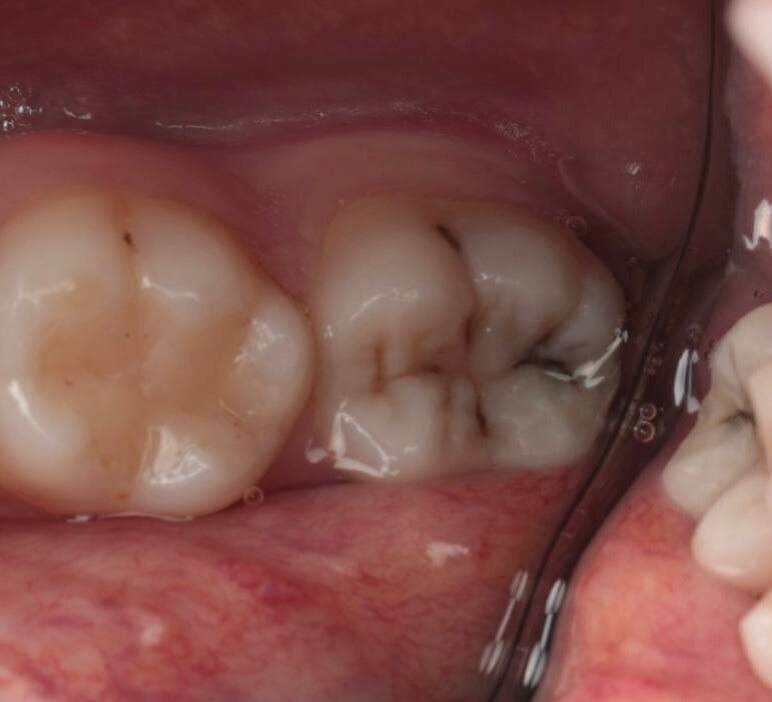

Нижняя восьмёрка, тот самый зуб мудрости, прорезалась одним-единственным бугорком, на фото его даже и не видать. Подленько!

На фото 6 и 7 - 8 даже не видно

Подобно айсбергу, массив тканей 8 зуба так и остался где-то там - как жИрный пИнгвин, в скалах застрявший. Места для нормального прорезывания, как водится, не хватило.

И вот этот одинокий прорезавшийся бугорок создал идеальную ловушку и кормушку для бактерий - глубокое ущелье между восьмым и соседним седьмым зубом. Костный карман со сложными бугристыми стенками, из которого вычистить остатки пищи не способна ни одна щётка в мире и ни один ирригатор. На ёршики тоже не надёйтесь.